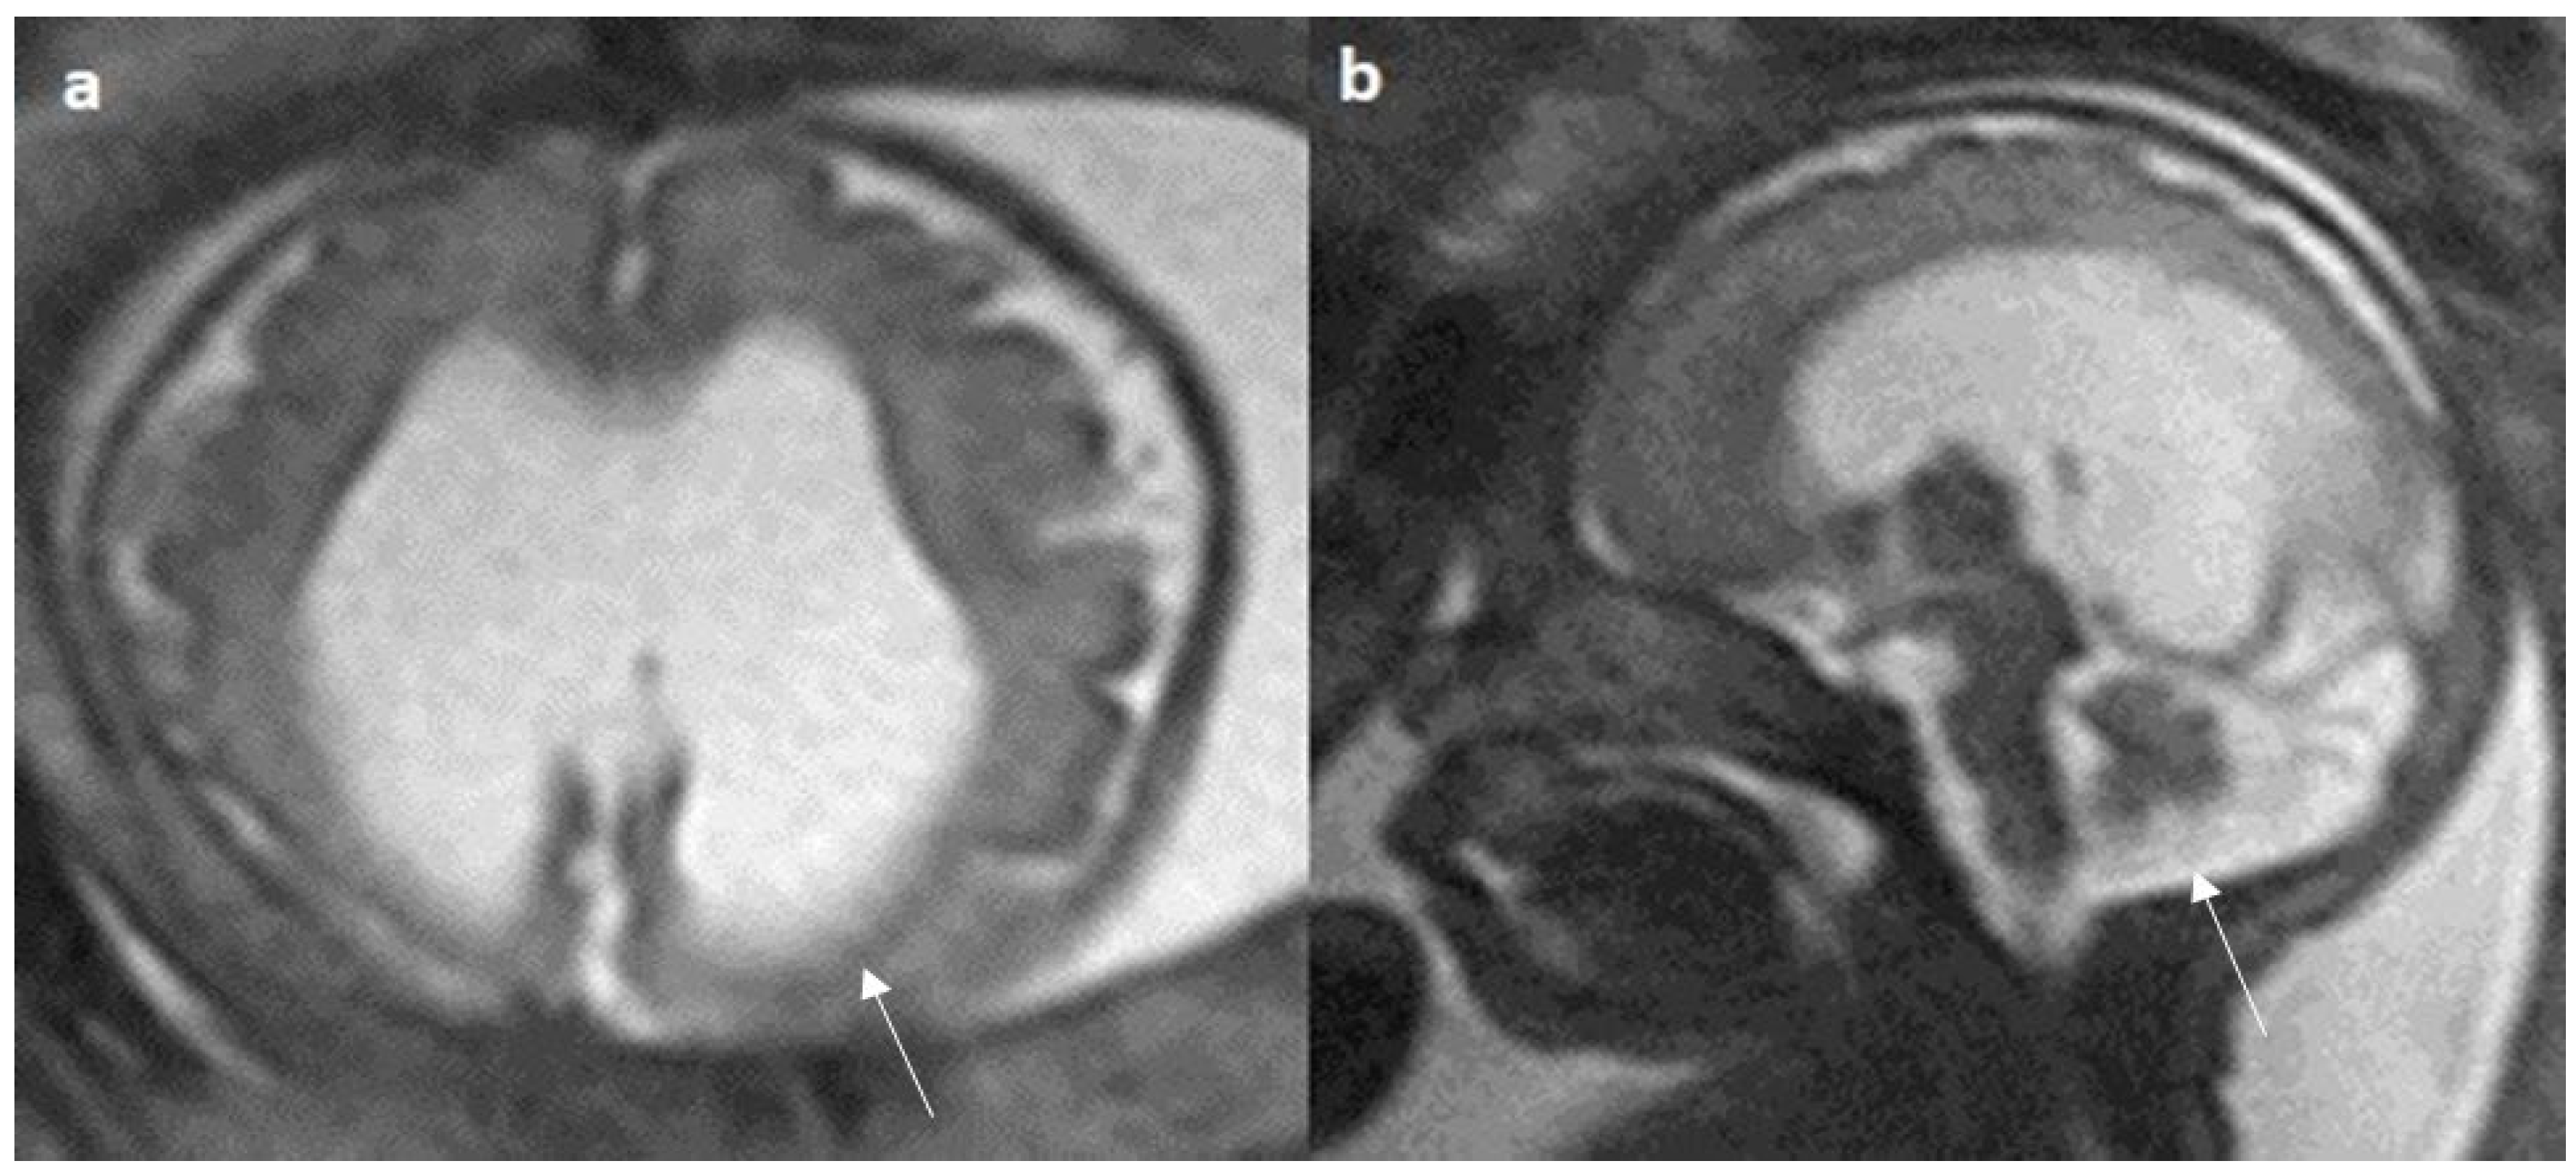

Associated CNS anomalies include 9/20 cases of interhemispheric cysts seen in 8 cases of complete agenesis and 1 case of hypoplasia. Out of 9 cases of IHC, 2 IHC were communicating with lateral ventricles. 4/20 (20%) cases had migration abnormalities such as gray matter heterotopia (Figure 8) in 3 cases of complete agenesis and hemimegalencephaly with schizencephaly in a case of dysplasia. 2 cases of cerebral cysts (2/20), including an arachnoid cyst in a case of complete agenesis class and a germinolytic cyst in a case of dysplasia. 3/20 cases of posterior fossa cysts, likely Blake’s pouch cysts, 2 in the complete agenesis class and 1 in the hypoplasia class. 2 cases of vermian hypoplasia (2/18) were noted, one each in the complete agenesis and hypoplasia classes (Figure 9 and Figure 10). A case of complete agenesis class had cerebellar hypoplasia and brain stem hypoplasia with a normal vermis. A case of complete agenesis class had a neural tube defect in the form of a sphenoidal meningoencephalocele. A case of dysplasia had diffuse thinning of white matter.

Figure 8.

Fetal MRI images of a 34 gestational weeks aged fetus, with complete agenesis of the corpus callosum and gray matter heterotopia. (a) A T2-weighted sequence image in mid sagittal plane showing complete absence of the corpus callosum with secondary changes in ventriculomegaly. (b) A T2-weighted axial sequence image showing associated subependymal heterotopia (white arrow) along the occipital horns of the bilateral lateral ventricles with moderate dilatation of lateral and third ventricles.

Figure 10.

Fetal MRI images of a 26 gestational weeks aged fetus with hypoplasia of the corpus callosum. (a) A T2-weighted sequence in mid sagittal plane image shows normal anterior part of corpus callosum with absent posterior part (arrow), suggesting hypoplasia of posterior region with anterior remnant, rest of the brain parenchyma in this section is normal. (b) A T2-weighted sequence in axial plane showing a small midline interhemispheric fluid collection/cyst without communication with the lateral ventricles.